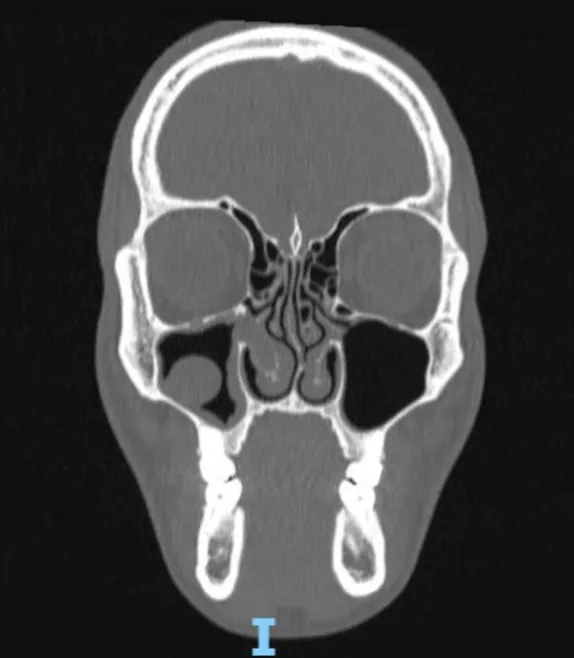

O Diagnóstico Preciso: O que os Exames Revelaram

Uma avaliação clínica e de imagem é fundamental para um planejamento cirúrgico completo. No caso deste paciente, os exames confirmaram os seguintes achados:

| Achado Clínico/Radiológico | Descrição | Impacto no Paciente |

|---|---|---|

| Desvio de Septo Nasal | O septo, parede que divide o nariz em duas fossas nasais, estava torto para a esquerda. | Causa principal da obstrução nasal. |

| Hipertrofia de Cornetos | Aumento dos cornetos (“carne esponjosa”), especialmente à direita. | Agravava a dificuldade respiratória. |

| Sinusopatia Crônica | Inflamação crônica no seio maxilar direito, com presença de um pólipo. | Explicava os episódios de sinusite. |

| Giba Osteocartilaginosa | Proeminência no dorso do nariz. | A “giba” que tanto o incomodava esteticamente. |

| Ponta Nasal Pendente | Ponta caída, sem definição e com aspecto pesado. | Principal queixa estética, a “ponta caída”. |

| Base Alar Alargada | Narinas com formato largo na visão frontal. | Contribuía para a desproporção facial. |